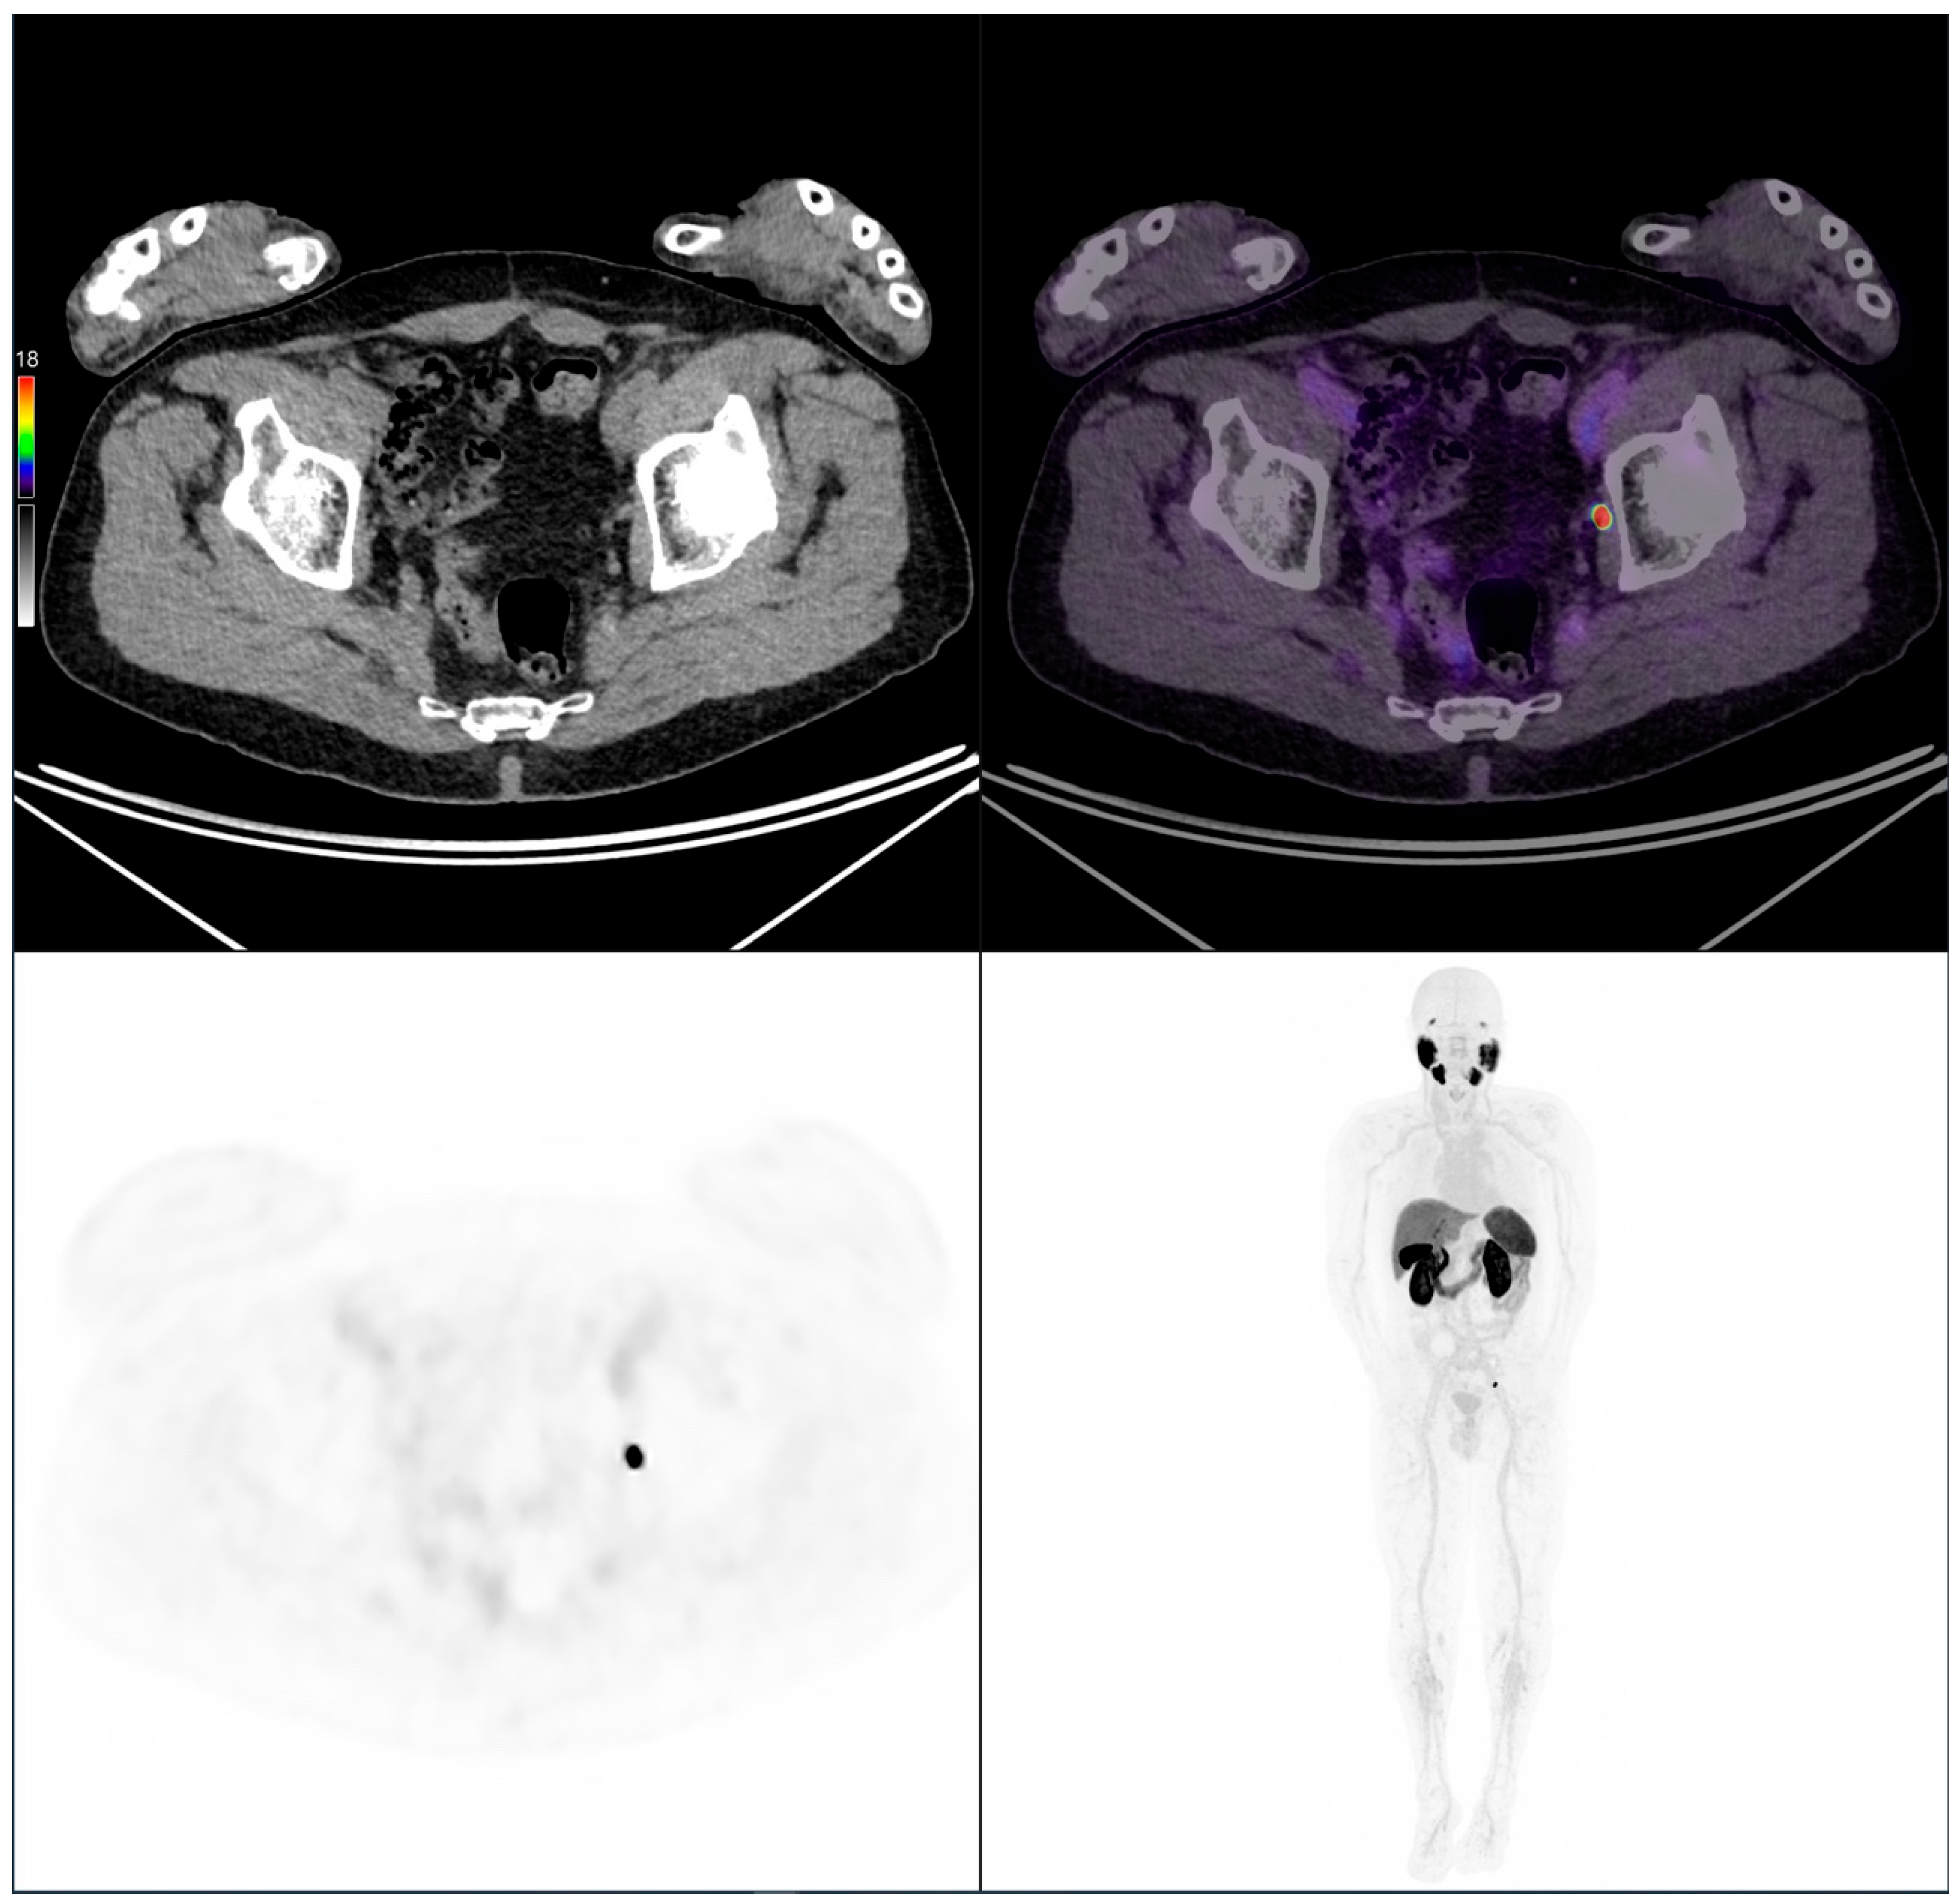

Figure 7.

PSMA PET/CT scan of an 83-year-old patient with biochemical recurrence (PSA: 0.4 ng/mL). Initially, the Gleason score was 4 + 3 = 7, pT3 pN0 M0, and treated with radical prostatectomy. Imaging performed following intravenous administration of 208 MBq of [18F]PSMA-1007 revealed a left obturator lymph node metastasis consistent with a local recurrence.